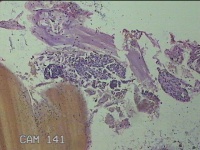

宫颈赘生物

性别

女

年龄

51岁

临床诊断

子宫多发性肌瘤 宫颈多发赘生物 宫颈息肉 子宫异常出血

一般病史

阴道断续流血数月余。

标本名称

大体所见

灰白暗红色肿物3x2.8x1.8cm一个,表面糜烂,切面灰白暗红色,质软。

图1